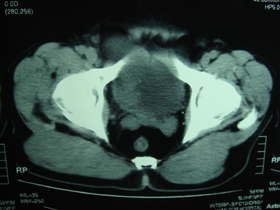

典型病例,男,56岁。无痛性血尿3月。

膀胱占位性病变,呈菜花状生长,考虑膀胱癌。 期待病理。